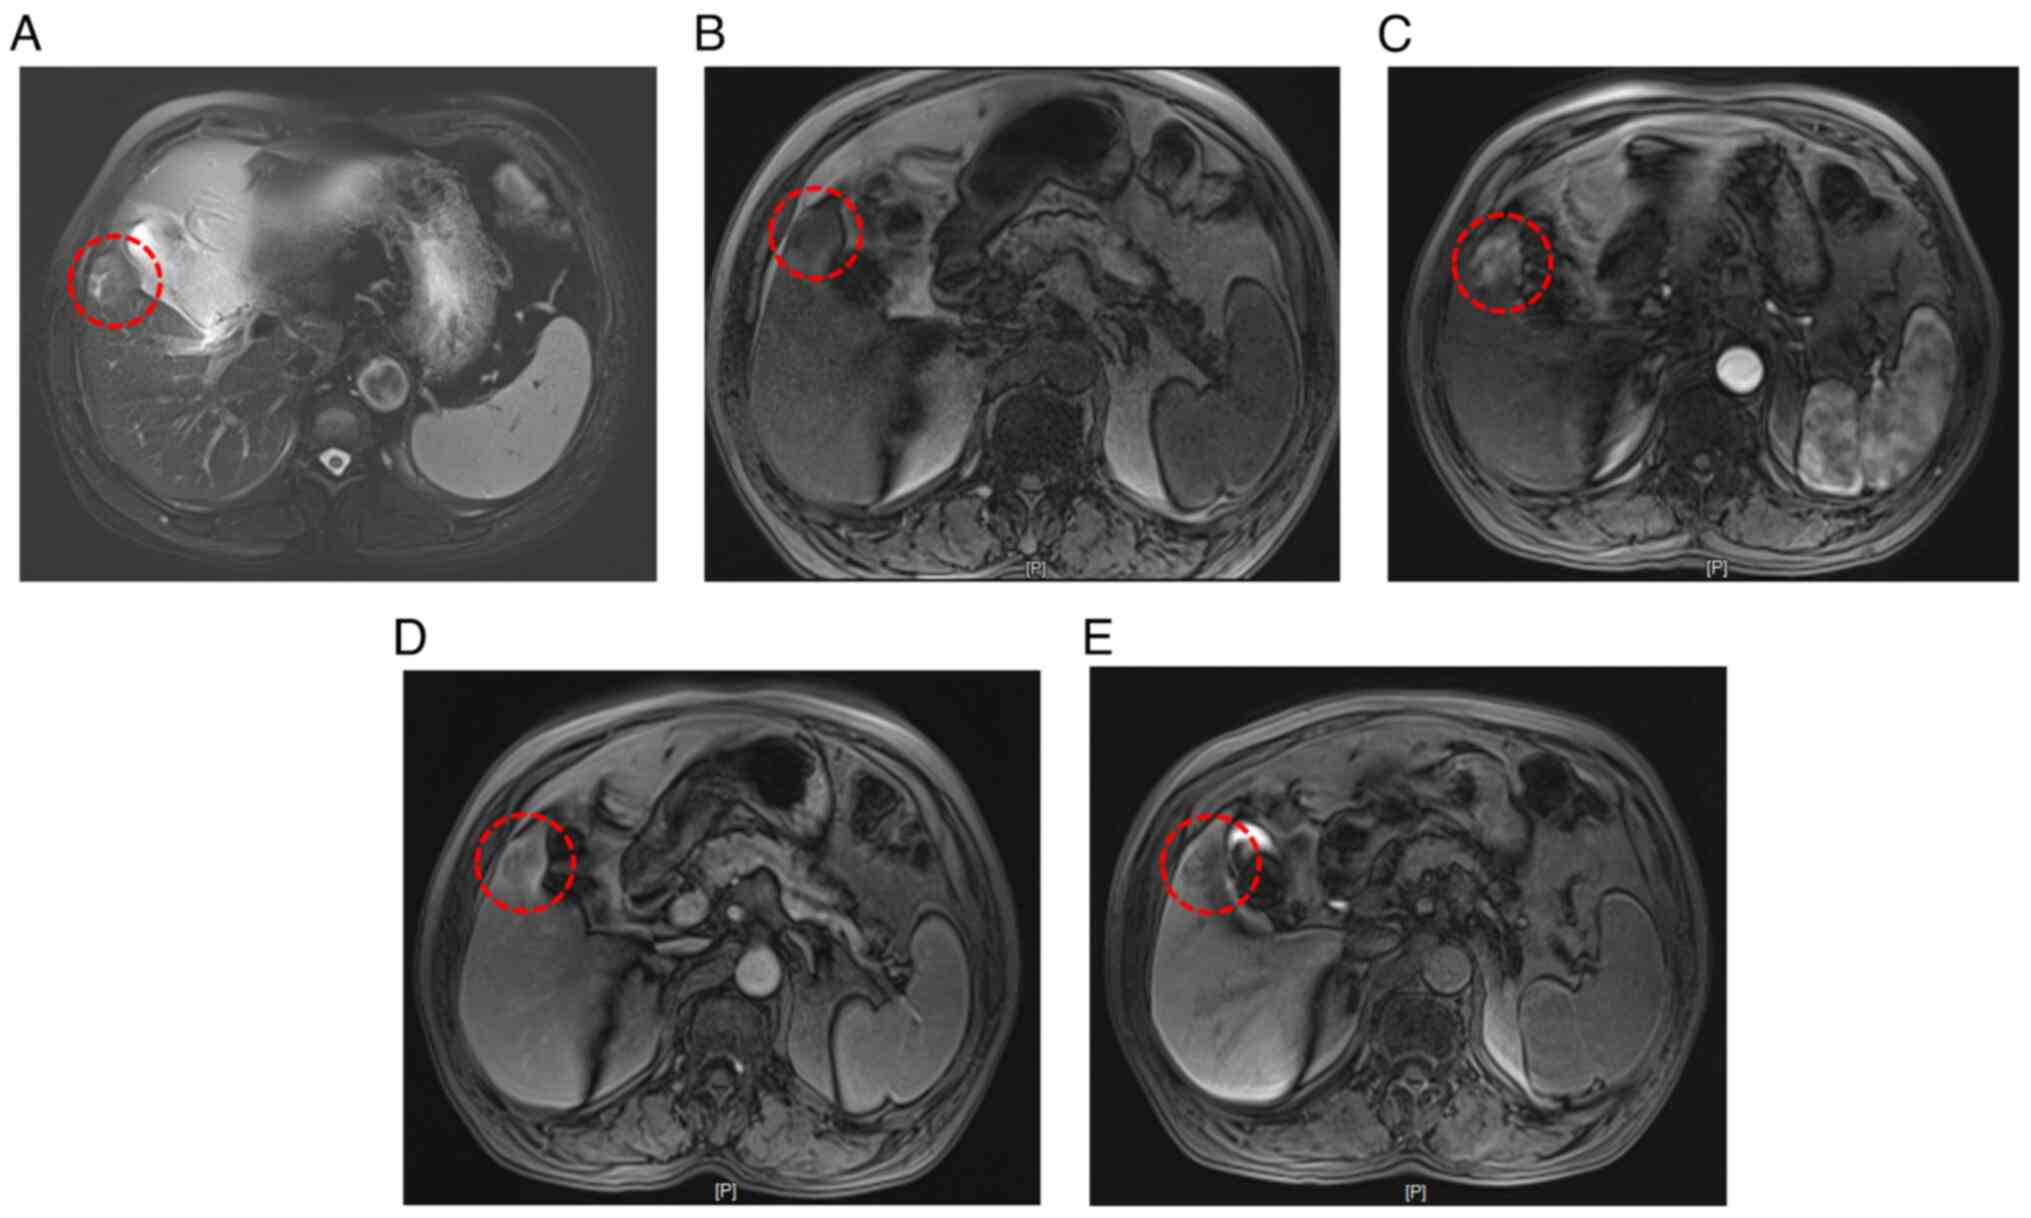

Figure 4.

Enhanced MRI examination suggests that the lesion in segment S5 of the liver is primary hepatocellular carcinoma. (A) A nodular slightly hyperintense signal is observed in the liver parenchyma of segment S5 on T2-weighted images (red circle). (B) A nodular slightly hyperintense signal is observed in the liver parenchyma of segment S5 on T1-weighted images (red circle). (C) The lesion in the liver parenchyma of segment S5 shows significant enhancement during the arterial phase (red circle). (D) The lesion in the liver parenchyma of segment S5 shows slight washout during the portal and delayed phases, with intensity lower than that of the surrounding liver parenchyma (red circle). (E) No significant enhancement of the lesion in the liver parenchyma of segment S5 is observed during the hepatobiliary phase (red circle).

A total abdominal enhanced computed tomography (CT) scan suggested a high likelihood of primary liver cancer and identified a stromal tumor on the lesser curvature of the stomach. Yellow circles highlight a lesion in the gastric fundus (Fig. 1). To further evaluate the gastric soft tissue lesion, gastroscopy was performed, revealing a neoplasm measuring 2.5 cm in diameter with a pedicle, alongside necrosis and ulceration on its surface (Fig. 2). A patchy, rough mucous membrane exhibiting a granular appearance was observed in the gastric angle but not seen under CT images, classified as type IIa + IIc according to the Japanese Research Society for Gastric Cancer (Fig. 3) (11). Narrow band imaging revealed local irregularities in glandular ducts and neovascularization. Pathological examination indicated high-grade dysplasia of the mucosal glandular epithelium, accompanied by chronic active inflammation, surface necrosis and erosion. Given the presence of tumors in both the liver and gastric angle, it remained uncertain whether the patient had synchronous primary tumors or a gastric tumor with liver metastasis. To clarify the diagnosis, an enhanced MRI with a liver-specific contrast agent (disodium gadoxelate) was conducted, confirming primary liver cancer in the S5 segment and early gastric cancer in the gastric angle (Fig. 4).

A gastroscopy and biopsy was performed first to determine high-grade dysplasia of mucosal glandular epithelium with chronic active inflammation, surface necrosis and erosion. Subsequently, enhanced MRI indicated primary gastric and liver cancer. Nodular long T1 and long T2 signals were seen in the S5 segment of the hepatic parenchyma, and the signals were slightly higher on diffused weighted imaging. The signal was markedly increased during the arterial phase following contrast administration, then slightly decreased in the portal and delayed phases, with intensity lower than that of the surrounding hepatic parenchyma. No marked enhancement was observed in the hepatobiliary phase, and the cross-section size of the neoplasm was ~2.0×2.4 cm, which was considered hepatocellular carcinoma. The final diagnosis depended on the postoperative pathology.

In the present case, the patient visited the hospital due to the presence of space-occupying lesions in the stomach and liver. In this case, the patchy, rough mucous membrane with a granular appearance in the gastric angle, classified as type IIa + IIc, indicated that the lesion displayed both elevated and depressed features, suggesting a complex lesion that could potentially have implications for diagnosis and treatment, including the possibility of malignancy. Pathological examination showed high-grade dysplasia of the mucosal glandular epithelium, making a definitive diagnosis of early gastric cancer difficult. However, the small early gastric carcinoma (gastric angle lesion) cannot easily be recognized on CT/MRI. Gastroscopy is the most effective way to detect early gastric cancer. Additionally, it was unclear whether the lesion in the S5 segment of the liver was a primary cancer or a metastatic lesion. Therefore, narrow-band imaging was performed, which showed irregular glandular ducts and neovascularization in the local area. Collectively, the lesion in the gastric angle was considered an early-stage lesion. Liver-specific contrast agent-enhanced MRI suggested that the liver lesion was highly likely to be primary liver cancer (18,19). The S5 space occupying lesion exhibited a ‘fast in and fast out’ appearance in the enhanced MRI; that is, the primary hepatocellular carcinomatosis was enhanced in the arterial stage, the liver tissue was strengthened in the venous stage suggesting primary hepatocellular carcinoma. The postoperative pathology test showed that the liver cancer exhibited characteristics of highly differentiated hepatocellular carcinoma without significant capsule invasion. Surrounding liver tissue showed no signs of cirrhosis; liver cell arrangement was regular, with localized hydropic degeneration of hepatocytes and infiltrates of chronic inflammatory cells, such as lymphocytes, in the portal area. The patient had a personal history of long-term heavy drinking and hypertension for 20 years, and fatty liver for 1 year. Therefore, there may be multiple possibilities for the degeneration. Regarding the levels of ALT and AST in the serum, these were normal. The most common explanation for why AST and ALT levels were normal is that a number of hepatitis B virus carriers have normal transaminase levels during annual physical examinations, but they can develop cirrhosis after a number of years. Based on the comprehensive examinations, the patient was diagnosed with synchronous primary liver cancer and early gastric cancer.